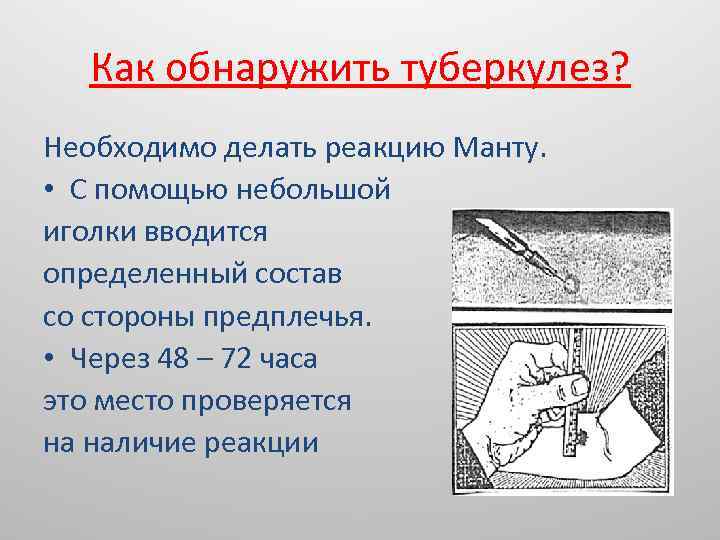

Симптомы и признаки туберкулеза: как распознать заболевание

Раздел: Визуальные уроки